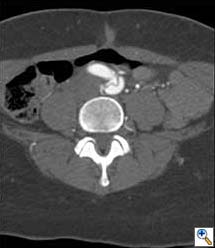

A 49-year-old woman with a history of hypertension and smoking presented to an outside hospital with sudden onset chest pain and hypotension. Computed Tomography/ Angiography (CTA) of the chest and abdomen revealed a type A aortic dissection extending from the ascending aorta to the left common iliac artery. (Figure 1) Of note, there was a significant pericardial effusion and left pleural effusion. Due to her hypotension and tamponade physiology, the patient was rapidly intubated followed by unsuccessful pericardiocentesis. The patient was then transferred to our institution for emergent dissection repair.

Figure 1a-e. Computed Tomography/Angiography (CTA) at

presentation demonstrating a type A aortic dissection.

Figure 1a. Axial CT at level of the pulmonary artery. The false lumen in the ascending aorta (white arrow) has minimal flow.

Figure 1b.

Figures 1b-d. Axial CT cuts demonstrating the dissection continuing into the left common iliac artery.

Figure 1e. Oblique sagittal CT reconstruction demonstrates the Type A dissection is complex with multiple fenestrations in the abdomen. Note bovine arch anatomy.